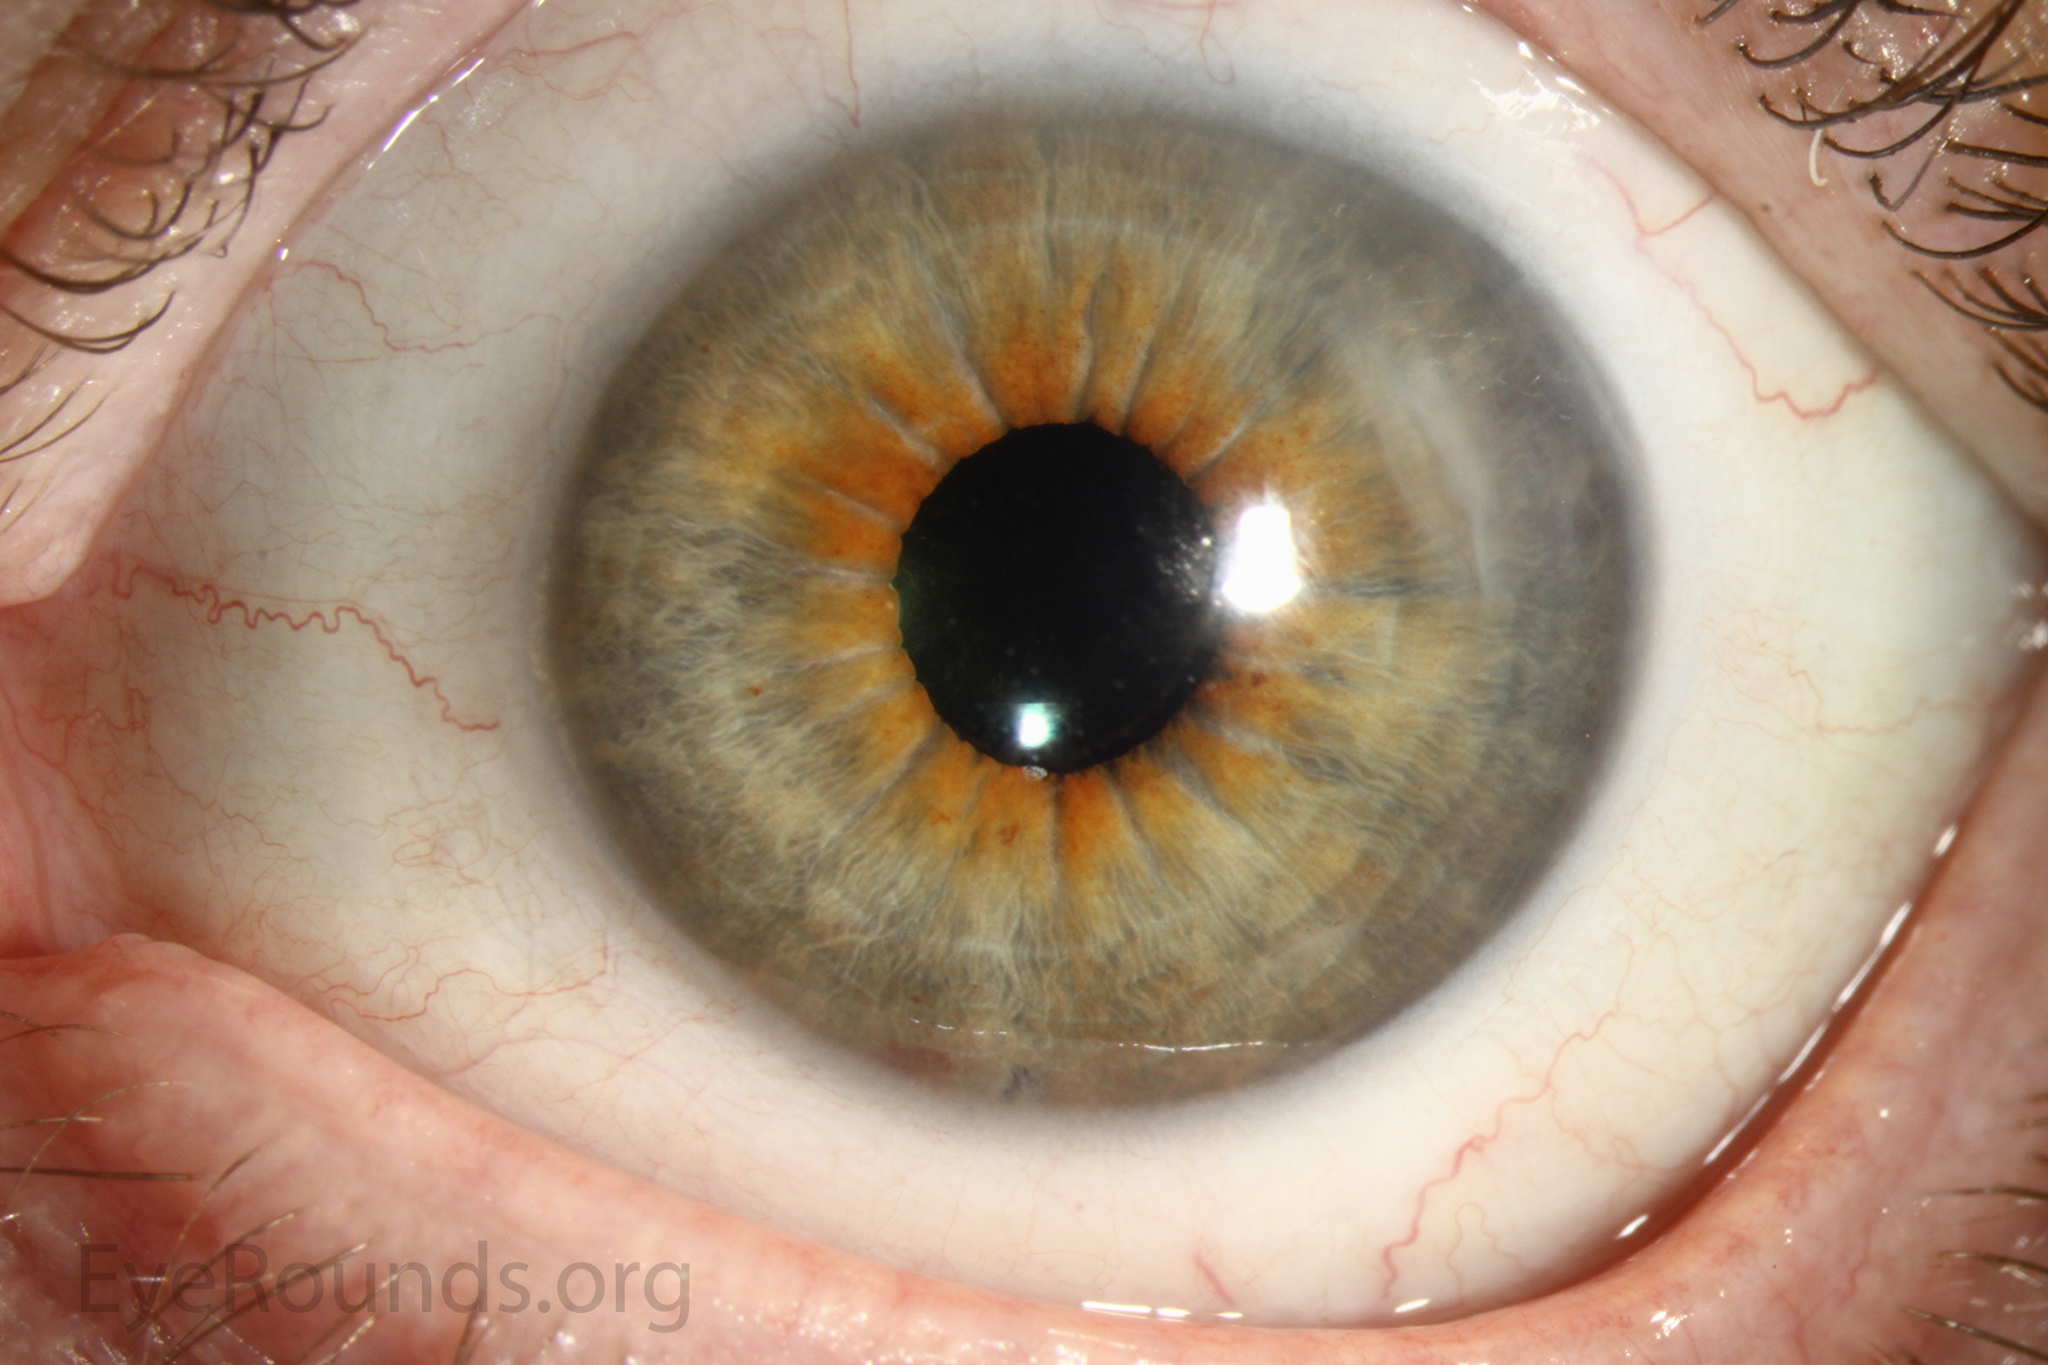

PK is a full-thickness transplant procedure, in which a trephine of an appropriate diameter is used to make a full-thickness resection of the patient's cornea, followed by placement of a full-thickness donor corneal graft. Interrupted and/or running sutures are placed in radial fashion at equal tension to minimize post-operative astigmatism (Figure 2). Later, the sutures are removed selectively to reduce the amount of astigmatism present. A transplant can last decades with proper care (Figure 3). While once the most prominent type of corneal transplant, PK has been supplanted by partial thickness techniques for endothelial dysfunction without significant stromal scarring. PKs are performed primarily for visually significant stromal scarring, opacities with an uncertain status of the endothelium or significant posterior corneal involvement, corneal ectasia (such as keratoconus and pellucid marginal degeneration, especially if there is history of hydrops), combined stromal and epithelial disease (such as Peters anomaly), and infectious or non-infectious corneal ulcerations or perforations (1, 14). A variant of the procedure, the mini-PK, can be used to treat more focal defects in the cornea (Figure 4).

Corneal transplantation is regarded as the most successful solid organ transplantation procedure (1). Niziol et al. performed a study in 2013 with follow-up averaging 10 years and found that corneal rejection after PK for keratoconus occurred in 44% of grafts, but only 8% of grafts actually failed (22). While long-term rejection data is not yet available for the newer EK procedures, lesser rejection rates have been demonstrated after DMEK (0.7%) and DSAEK (9%) than PK (17%) at 2 years in patients on the same postoperative steroid regimen and treated for similar indications (23). This may be secondary to reduced antigen load in the thinner graft tissue. Modern treatment efforts can account for the vast difference between graft rejection and failure. However, graft rejection still remains a significant cause of corneal graft failure (Figure 16) (1). The most effective intervention is early recognition and prompt treatment with topical steroid drops. If the patient notices any redness, pain, or decreased vision, it is critical to seek prompt treatment to maximize chances of reversing the rejection episode.